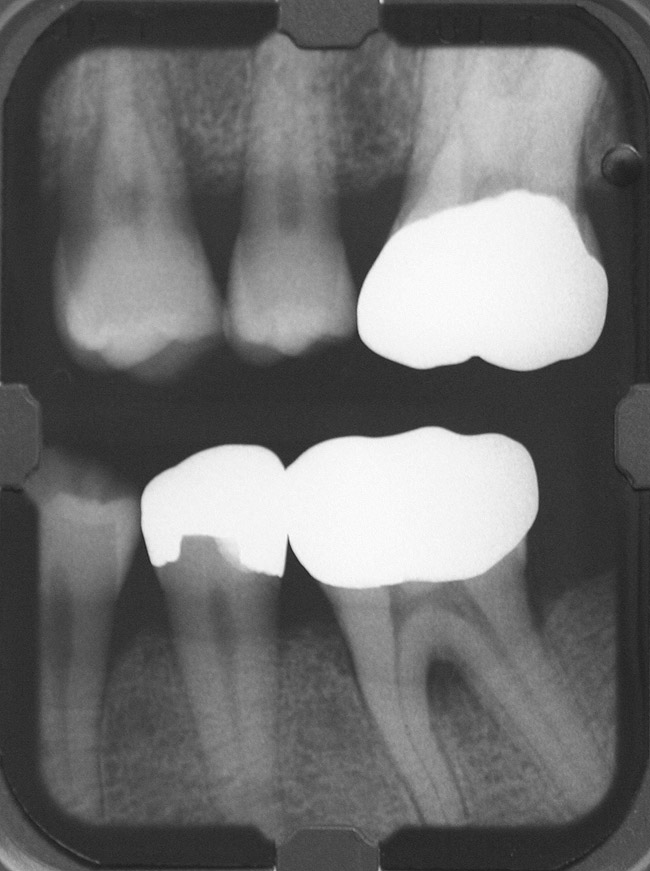

Inflammation limited to soft tissues around a dental implant may result from dental plaque colonization and is termed peri-implant mucositis. This is a reversible inflammatory condition limited to the soft tissues around the implant (without any bone loss), analogous to gingivitis around natural teeth. A diagnosis of peri-implantitis results when the inflammation spreads apically, causing progressive loss of osseointegrated supporting bone, analogous to periodontitis around natural teeth16 (Figure 2A and Figure 2B). It is essential for practitioners to be familiar with these diagnostic terms when assessing the long-term success of implants and peri-implant health (Table 1).

Figure 2a

Figureb 2  (A) Clinical and (B) radiographic views of implants at site Nos. 30 and 31 demonstrating bone loss caused by peri-implantitis after 8 years in function. Note gingival inflammation and plaque accumulation around implants.